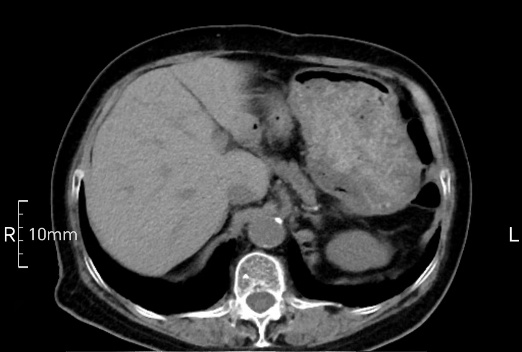

看看下面三幅便知遵醫(yī)囑的重要性。

沒禁食,胃內(nèi)全是食物,導致胃壁顯示不清。